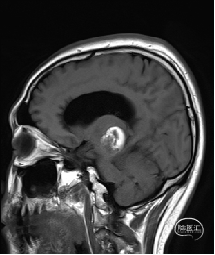

术前MRI检查

术前MRI检查提示左侧丘脑中脑海绵状血管瘤并卒中,梗阻性脑积水;

诊断:1.左侧丘脑中脑海绵状血管瘤并卒中,2.梗阻性脑积水;

年轻患者,较短时间内发生左侧丘脑二次出血,出现右侧面部及上肢麻木,复视,第二次出血后并发梗阻性脑积水,出现头痛。结合病史、神经系统体征、头颅CT及MRI检查,诊断左侧丘脑及中脑CM并卒中、脑积水明确,并导致了神经功能障碍,具备手术指征。

本例患者磁共振检查清晰显示病变位于左侧丘脑中脑区域,且位于丘脑内下方向中脑顶盖延续,病变的上部、前部、外侧部都有重要的神经组织,因此,手术从上方、前方、外侧方向切除病变均难以实施;